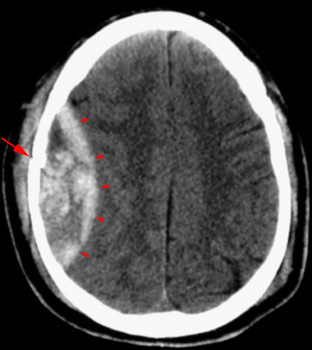

Head CT > Trauma > Epidural Hematoma

Epidural Hematoma

An epidural hematoma is usually associated with a skull fracture. It often occurs when an impact fractures the calvarium. The fractured bone lacerates a dural artery or a venous sinus. The blood from the ruptured vessel collects between the skull and dura. On CT, the hematoma forms a hyperdense biconvex mass. It is usually uniformly high density but may contain hypodense foci due to active bleeding. Since an epidural hematoma is extradural it can cross the dural reflections unlike a subdural hematoma. However an epidural hematoma usually does not cross suture lines where the dura tightly adheres to the adjacent skull.